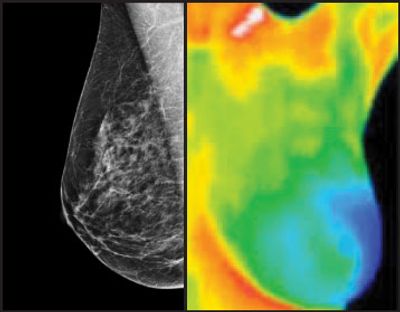

Recent published studies have demonstrated a rather low benefit to routine screening with X-ray mammography and many serious adverse complications (2, 3). The 2009 US Preventive Services Task Force could not determine any meaningful benefit to routine screening X-ray mammography for women less than fifty years of age or for screening X-ray mammography more than every other year for women between ages fifty and seventy-four (4). Every woman is at risk for breast cancer and the inadequacies of screening X-ray mammography to save lives should not diminish the importance to screen women younger than fifty years or between biennial X-ray mammograms. While screening X-ray mammography remains the standard of care, we assert that it is insufficient as a stand-alone modality due to its insensitivity for large populations of at-risk women and a very high rate of false-positive results.

The high sensitivity of thermology for younger women and its absolute safety are compelling reasons to indicate routine screening thermology for women under fifty years of age and in the year between routine screening X-ray mammograms for women between fifty and seventy-four years of age (5).